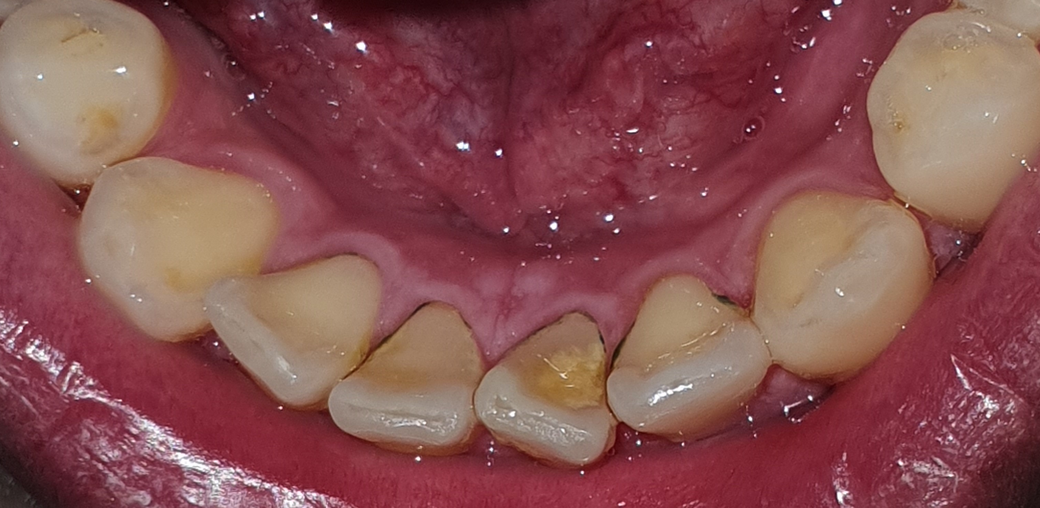

이와 잇몸사이 검은색 줄 같은게 생겼습니다 도와주세요

최근에 갑자기 이와 잇몸을 맞닿는곳에 검은색 줄 같은것들이 생겼습니다

밑 앞니 두개와 옆에이 양쪽에 생겼는데 맨처음에는 초록색으로 보여서

시금치인줄 알고 치실을 했으나 안없어지고 잇몸에 피만 나오더군요

통증은 없습니다

치석이 쌓인거 같습니다. 치과에 가셔서 스켈링 및 잇몸치료를 받아보시는게 좋을것같습니다. 일단 치과에가셔서 검진을 받아보세요

흡연을 하는 경우 니코틴이나 타르색소가 침착되었을 가능성이 있으며, 우선 치과에 방문하여 진료를 받고 상태 파악후에 스케일링 및 잇몸 치료를 받길권합니다.